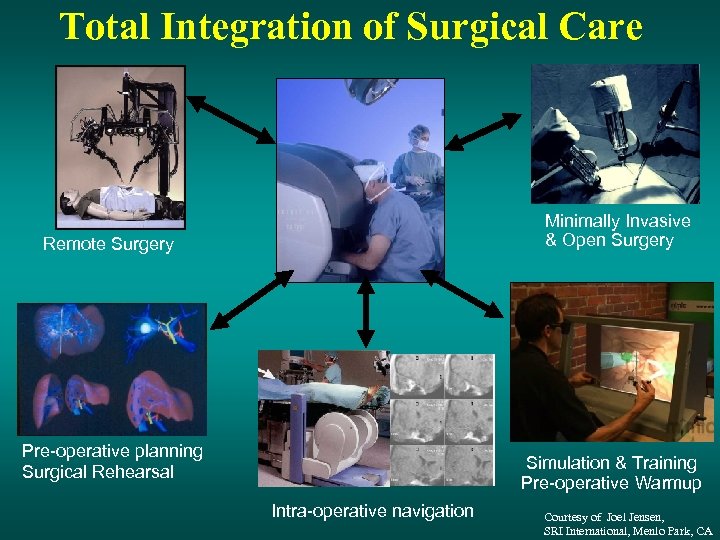

Total Integration of Surgical Care Minimally Invasive & Open Surgery Remote Surgery Pre-operative planning Surgical Rehearsal Simulation & Training Pre-operative Warmup Intra-operative navigation Courtesy of Joel Jensen, SRI International, Menlo Park, CA

Total Integration of Surgical Care Minimally Invasive & Open Surgery Remote Surgery Pre-operative planning Surgical Rehearsal Simulation & Training Pre-operative Warmup Intra-operative navigation Courtesy of Joel Jensen, SRI International, Menlo Park, CA

Total Integration of Surgical Care Minimally Invasive & Open Surgery Remote Surgery Pre-operative planning Surgical Rehearsal Simulation & Training Pre-operative Warmup Intra-operative navigation Courtesy of Joel Jensen, SRI International, Menlo Park, CA

Total Integration of Surgical Care Minimally Invasive & Open Surgery Remote Surgery Pre-operative planning Surgical Rehearsal Simulation & Training Pre-operative Warmup Intra-operative navigation Courtesy of Joel Jensen, SRI International, Menlo Park, CA